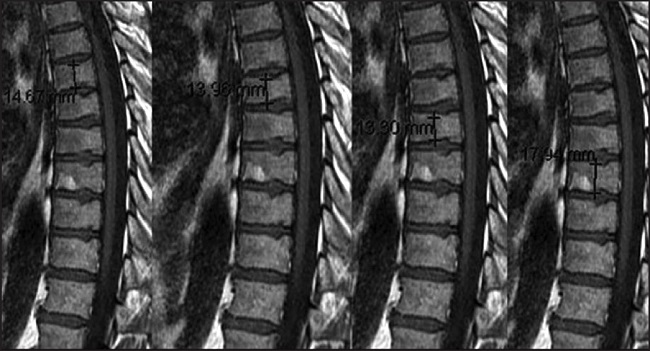

Resultados: Se incluyeron 614 pacientes (marzo 2009-febrero 2018), de los cuales se han analizado 219 que han realizado una segunda y tercera visita. La media de edad fue de 64 años, con una media de índice de masa corporal del 28,57 Kg/cm2. En la primera visita la media de DMO (1DMO) fue de 0,885 g/cm2 y de 1TBS de 1.260 g/cm2; un 50,8% no iniciaron tratamiento antiresortivo, 34,2% inició bis-fosfonatos orales, 4,4% endovenosos y 5,7% denosumab subcutáneo. En la segunda visita, la media de 2DMO fue de 0,873 g/cm2 y de 2TBS de 1.249 g/cm2; 8,4% inició bisfosfonatos (orales 39 y endovenosos 12) y 2,8% denosumab (17). La gráfica muestra la evolución de la cantidad y calidad de masa ósea sin tratamiento y con tratamiento antiresortivo (Figuras 1 y 2).

Discusion-conclusio-nes: En los pacientes con tratamiento antire-sortivo se observa una evolución adecuada y diferente tanto en la cantidad (DMO p<0,003) como en la calidad ósea (TBS p<0,074) de la columna lumbar. La DMO y la TBS son herramientas útiles para moni-torizar los cambios de salud ósea en estas pacientes con neoplasia de mama y tratamiento con IA.